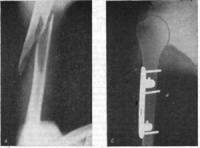

При наличии в зоне перелома осколков средней или крупной величины их фиксируют к ложу на кости одной или двумя спицами с упорными площадками .

При невозможности по каким-либо причинам провести спицы вышеописанными способами, осколки могут быть фиксированы спицами,проведенными транскортикально или параоссально .

В последнее время для фиксации осколков мы стали использовать консольные спицы с упорными площадками, расположенными на расстоянии 2-2,5 см от их острого конца